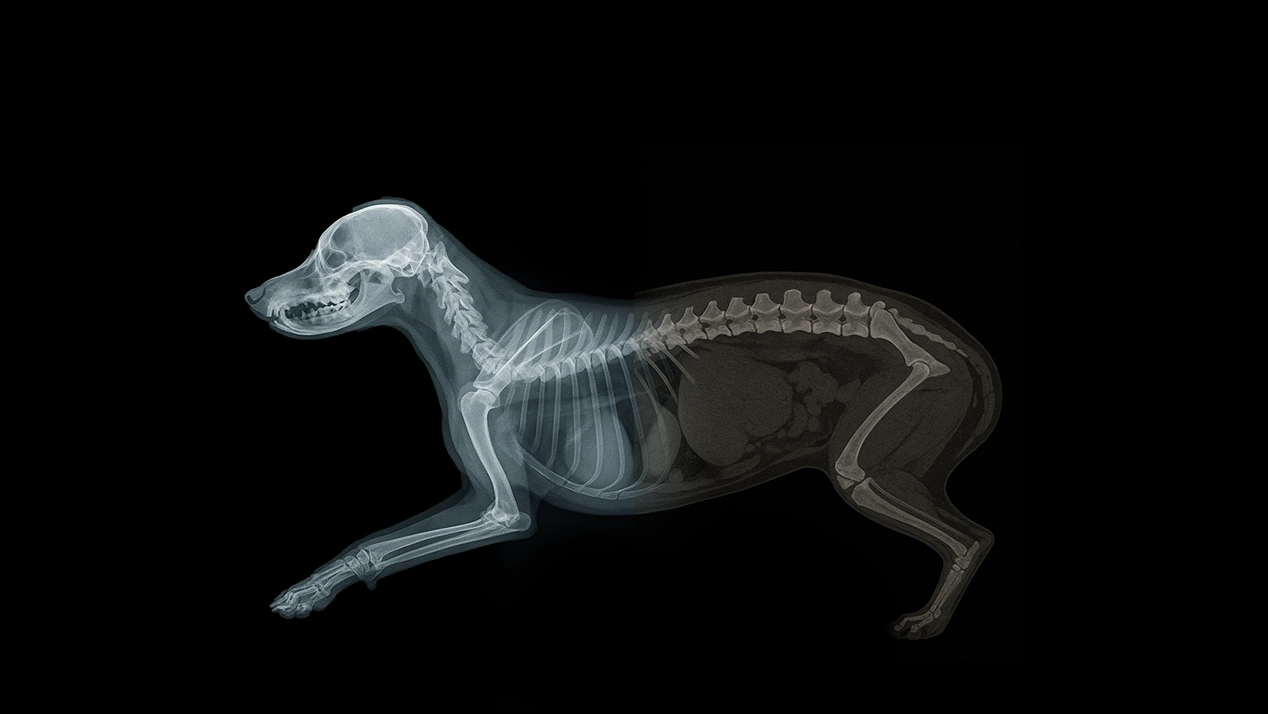

- Anatomia aplicada na análise do esqueleto axial

- Anatomia aplicada na análise do esqueleto apendicular

- Anatomia aplicada na análise do tórax

- Anatomia aplicada na análise do abdômen